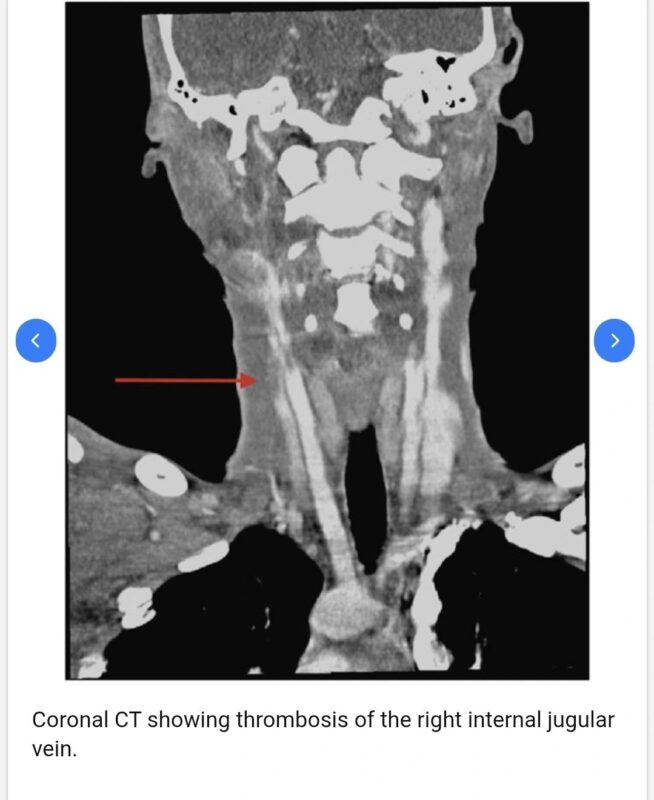

CT neck shows thrombosis of the right internal jugular vein with surrounding soft – tissue infection.